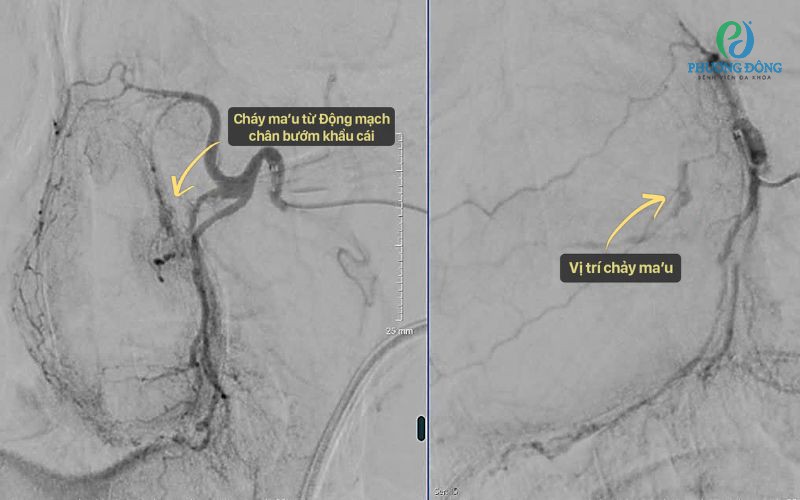

Tại Trung tâm Chẩn đoán hình ảnh và Điện quang can thiệp Quốc tế Phương Đông, bệnh nhân được chỉ định chụp mạch bằng hệ thống DSA (chụp mạch số hóa xóa nền). Kết quả cho thấy nguyên nhân xuất phát từ nhánh động mạch hàm trong - cụ thể là động mạch bướm khẩu cái, vị trí sâu và khó tiếp cận.

Thay vì can thiệp phẫu thuật lần hai, các bác sĩ đã lựa chọn phương pháp nút mạch - một kỹ thuật ít xâm lấn nhưng đem lại hiệu quả cao. Thông qua một ống thông siêu nhỏ, ekip can thiệp tiếp cận chính xác vị trí tổn thương và bơm vật liệu chuyên dụng để “khóa” dòng chảy.